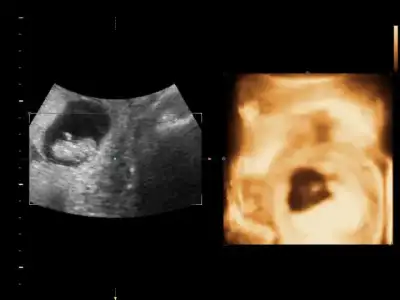

Kıza benziyor bence.Fikri olan var mı acabaEki Görüntüle 1530236

Kiz bence cikinti yokFikri olan var mı acabaEki Görüntüle 1530236

Canım kıza daha çok benzettim ben :)